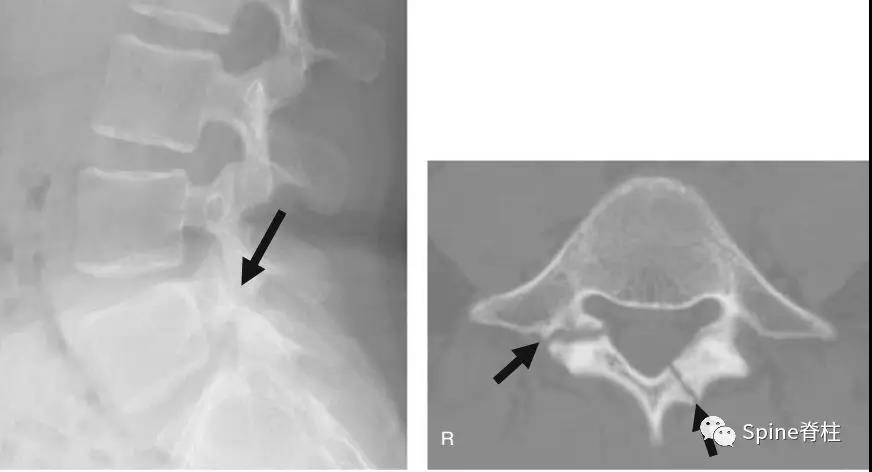

图:L5半椎板裂15岁篮球运动员,严重腰痛,影响睡眠CT示:左侧为椎板裂(箭头),右侧为峡部裂(箭头)